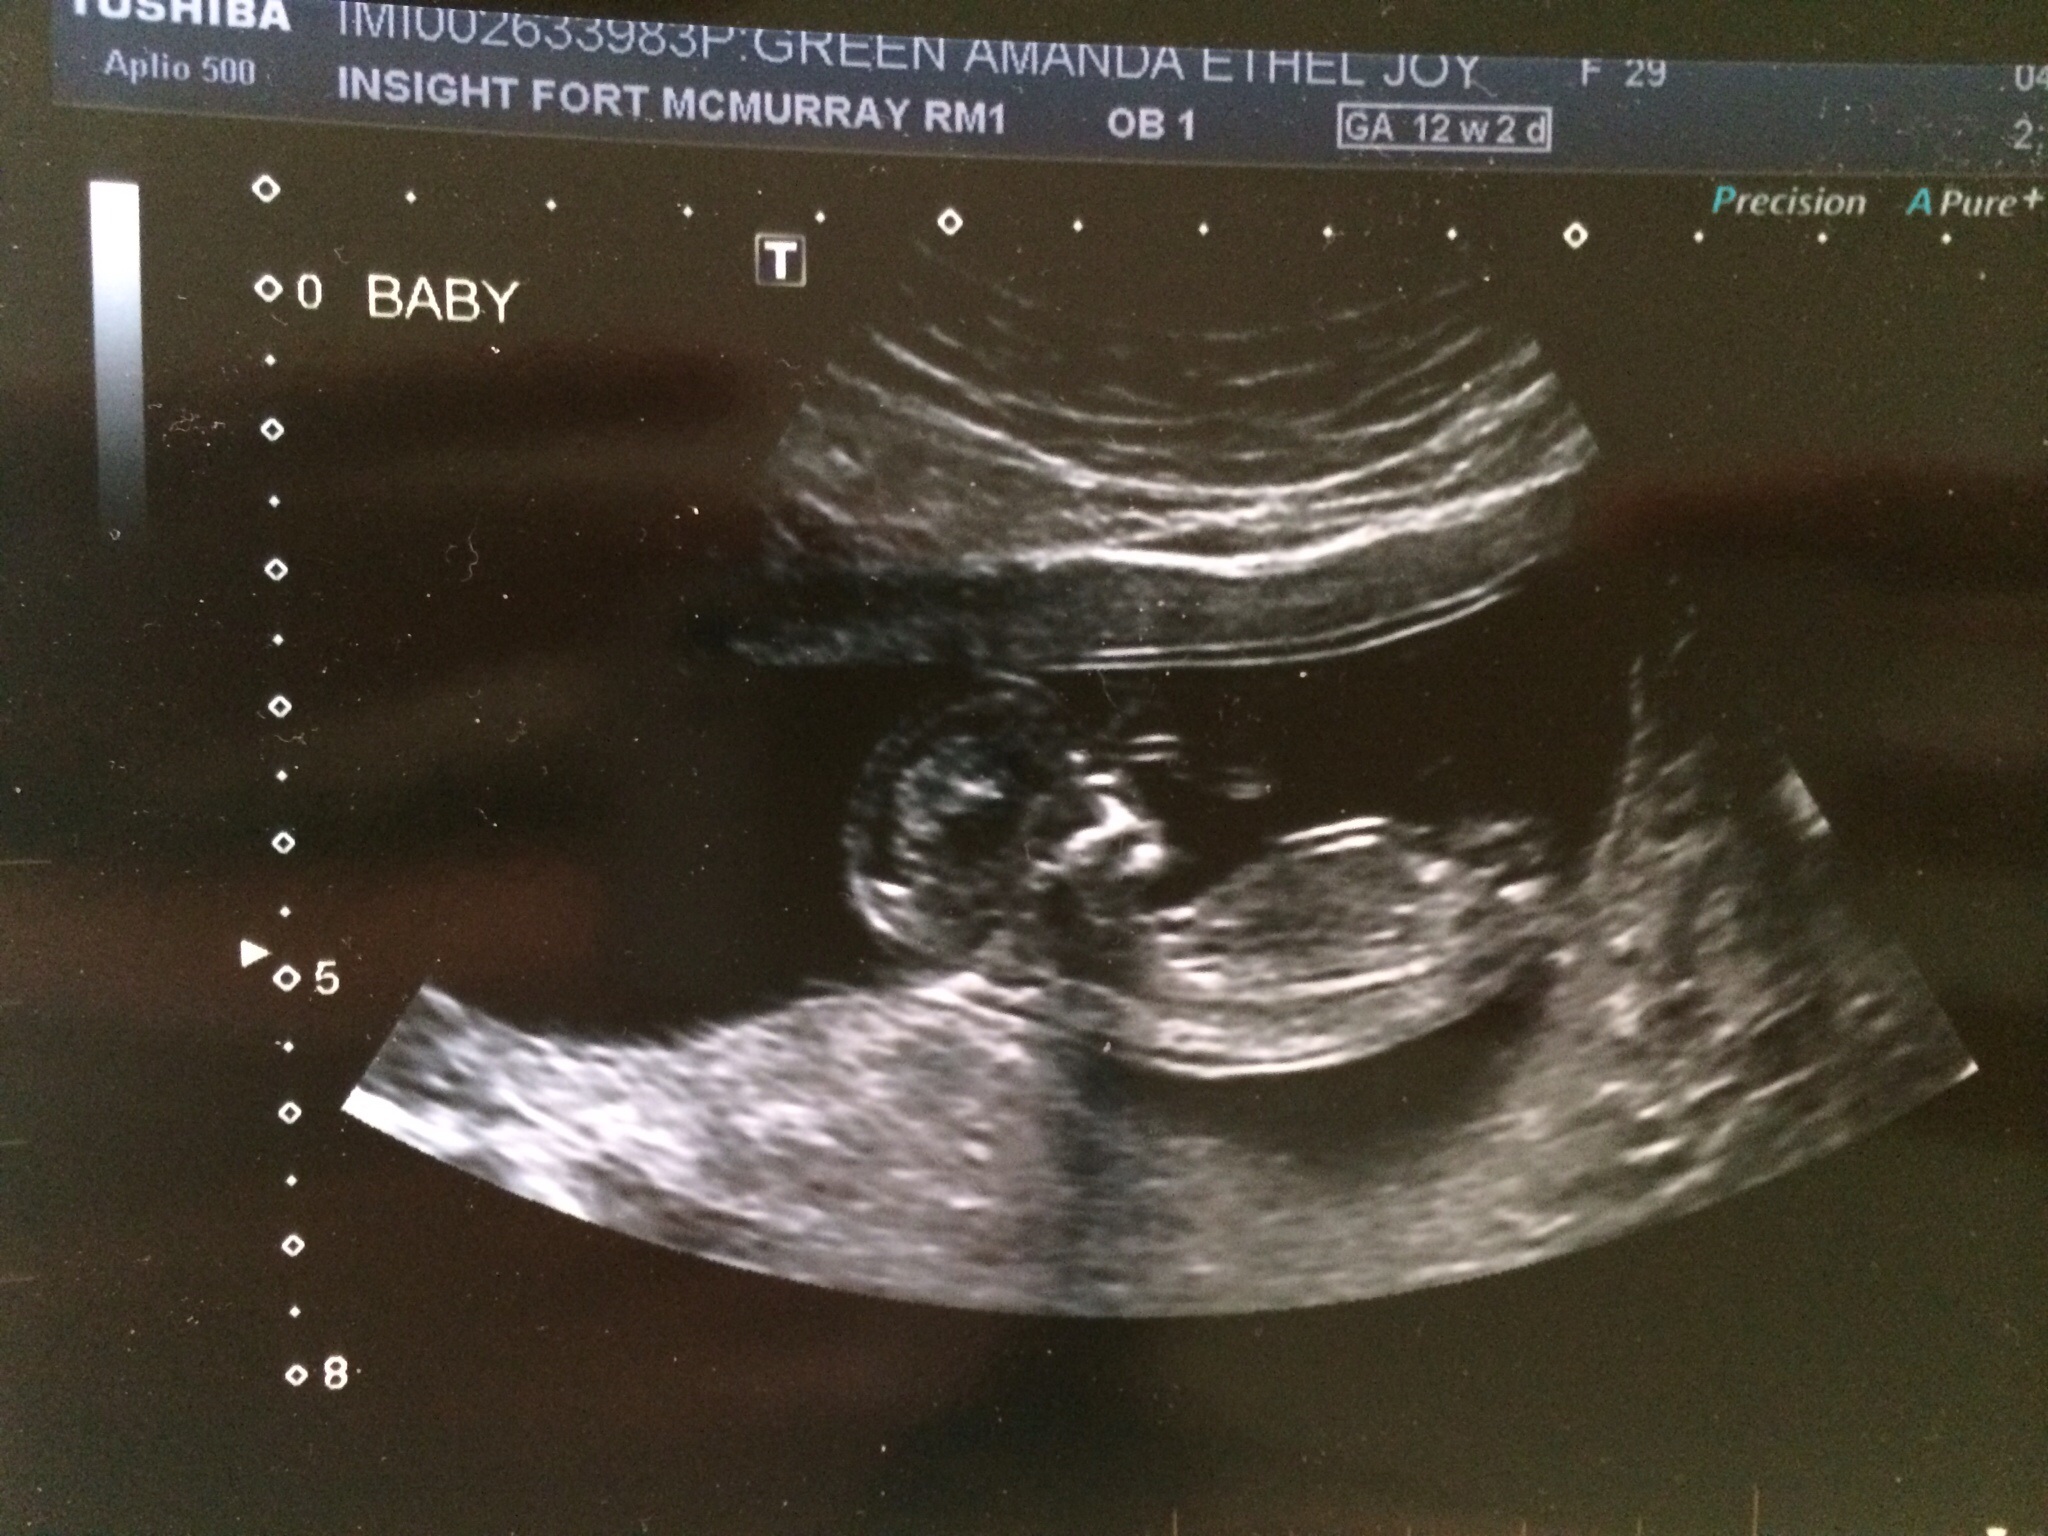

12w2d baby measuring at 12w5d! What is a girl nub? Also my uterus looks shaped different than everyone else's... Either way we are ecstatic and it's amazing how human she/he looks already! Strong heart beat of 166bpms!!